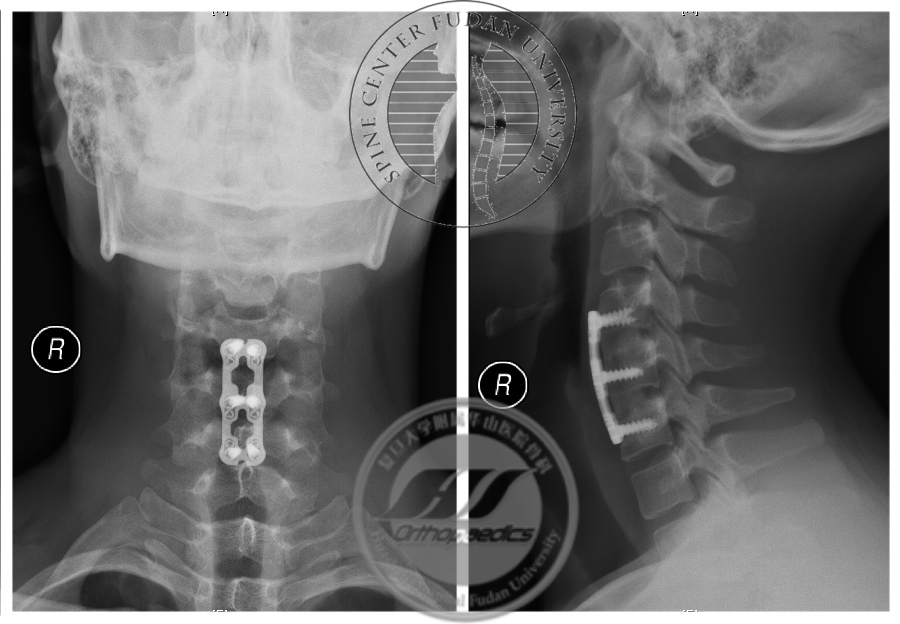

患者于2017年8月30日接受颈椎前路自体髂骨植骨融合内固定术,术后恢复良好,定期随访。最近一次随访为2019年9月(术后2年),患者诉右手握力较前增大,寒冷时症状较前好转,伸指震颤症状仍存在。X线示内固定无松动移位,屈颈位MRI显示“膜-壁分离”现象消失,屈颈位脊髓未见明显压迫,相邻节段未见明显退变(图6,7),神经电生理检查示所检肌自发电位消失,募集较前好转(图8)。

图6 术后2年X线示内固定无松动移位,颈椎曲度良好

图7 术前与术后2年屈颈位MRI对比,术后T2加权像显示“膜-壁分离”现象消失